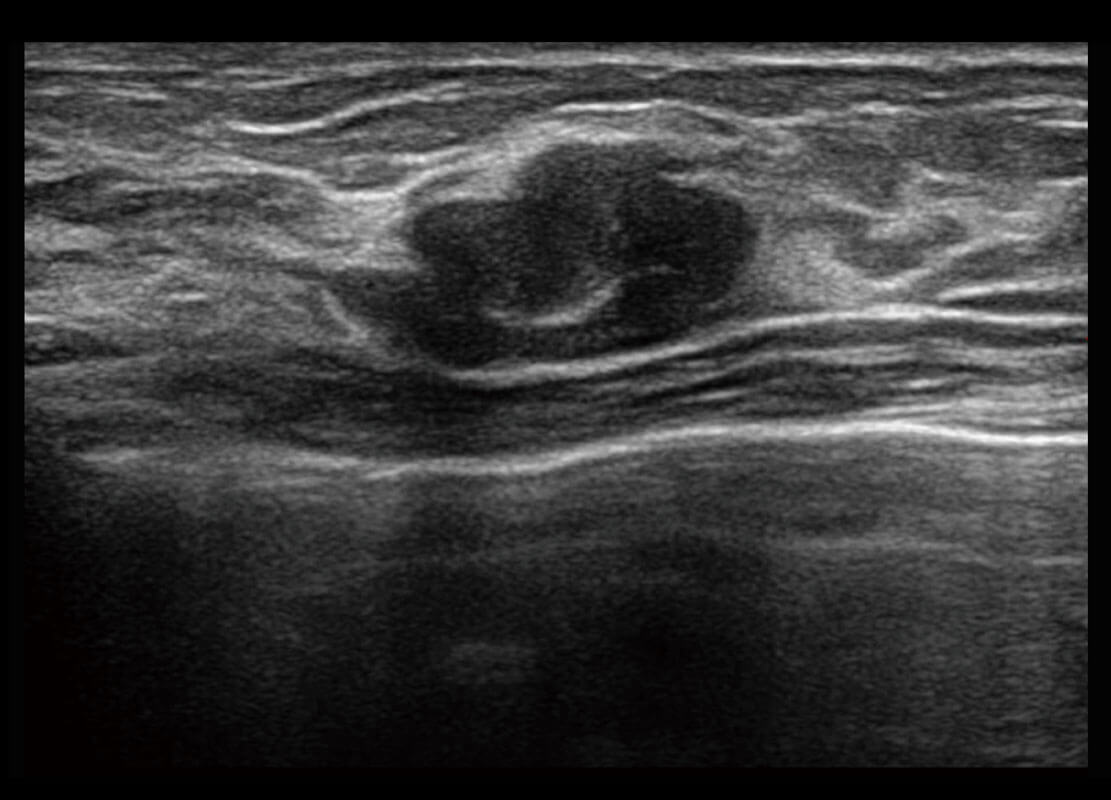

P60优异的图像质量搭载专科探头,在妇科基础疾病的诊断、卵泡生长的监测、输卵管通畅情况的判别等方面为您提供生殖应用方案。

腔内妇科-卵巢

P60搭载宽频带线阵探头、宽景成像、弹性成像技术,为您提供乳腺应用方案。P60支持高频相控阵探头、线阵探头、腹部高频探头、腹部微凸探头等,丰富的探头群搭载敏感的彩色血流成像,适用于新生儿多种脏器检测要求,满足新生儿筛查需求。

乳腺导管癌

乳腺癌显微血流